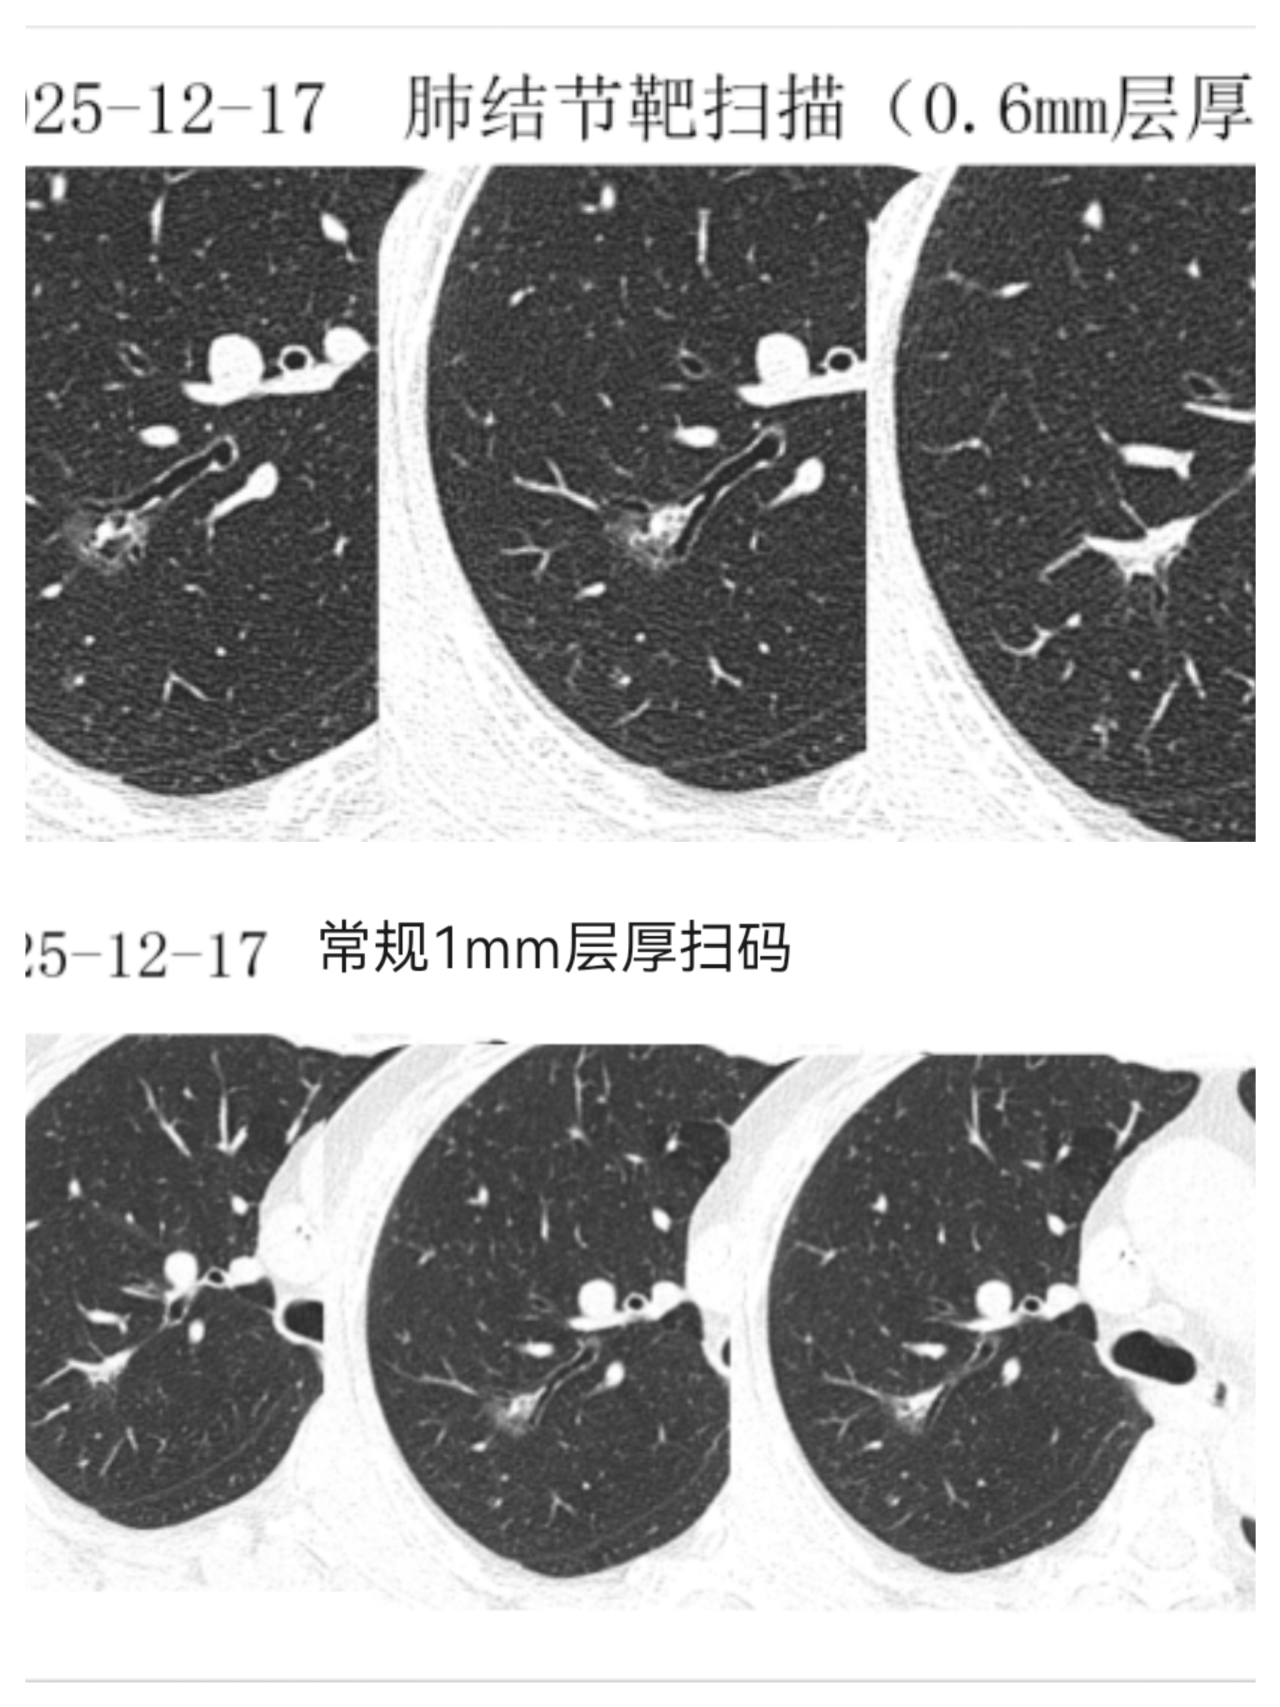

一、胸部肿瘤诊疗:突破技术瓶颈,提升救治能力 高龄食管癌手术自主完成 面对高龄患者手术高风险挑战,科室独立完成82岁食管癌根治术,全程自主把控手术操作与围术期管理,患者术后恢复良好。此次手术标志着我院胸部外科麻醉、医疗及护理体系日趋成熟,为食管肿瘤患者提供了新的治疗选择。 局部晚期肺癌手术稳步推进 针对局部晚期肺癌患者,科室凭借精准的手术规划与精细化围术期管理,成功完成多例手术,为患者争取了治疗时机与生存机会。 转化治疗策略改善晚期肺癌预后 对于初始不可手术的晚期肺癌患者,对接前沿技术,联合肿瘤科开展化疗联合免疫治疗的“转化治疗”策略,成功缩小肿瘤体积并实现降期,最终通过外科手术完整切除病灶。该案例体现了我院MDT团队协作优势,为晚期肺癌患者开辟“带瘤生存”向“无瘤生存”转化的路径。 后纵隔肿瘤诊疗能力提升 先后完成“后纵隔巨大肿瘤综合治疗”“后纵隔复杂肿瘤外科切除”等手术,推动肿瘤综合治疗水平稳步提升。 二、甲状腺疾病诊疗:微创与美容结合,优化治疗体验 腔镜甲状腺手术实现“无痕化”进展 引进“腋下美容切口”“胸乳入路腔镜手术”等技术治疗甲状腺肿瘤,在保证疗效的同时减少手术创伤,兼顾患者美观需求,标志着科室在微创技术道路上迈出坚实步伐。 复杂胸腺肿瘤微创治疗落地 成功开展“剑突下切口微创胸腺肿瘤切除术”,通过微小切口完成深部肿瘤精准切除,术后患者疼痛轻、恢复快,为胸腺肿瘤患者提供新的治疗选择。 三、乳腺疾病诊疗:精准与人文并重,守护女性健康 乳腺癌一体化诊疗模式逐步完善 科室推进早期乳腺癌保乳手术开展,对晚期乳腺癌实施新辅助治疗后再手术,建立“筛查-诊断-治疗-康复”一体化诊疗模式,让患者在家门口就能享受便捷医疗服务。 四、血管与功能性疾病:微创技术解难题,提升患者满意度 功能性疾病微创治疗优化 在腋臭、手汗症等功能性疾病的微创治疗中,科室采用mini切口无痕手术、胸腔镜下交感神经切断等技术,术后效果明显且疤痕隐蔽;静脉输液港植入为肿瘤患者建立“生命通道”。 下肢静脉曲张治疗技术升级 推广“外科微创下肢静脉曲张治疗+硬化剂注射”等新技术,兼具美容、高效优势,对晚期合并溃疡患者效果明显。 五、多学科协作(MDT):强强联合,攻克复杂病例 高危复杂病例协作救治成功 面对颈部巨大肿物压迫导致顽固性高血压、心脏功能恶化的高危患者,科室联合心血管内科、麻醉科组建MDT团队,术前植入临时起搏器保障心脏安全,术中全程严密监护,最终精准切除肿瘤。该案例体现了我院在颈部神经血管危险区多学科协作的能力。 肺结节MDT诊疗方案落地 健全肺结节多学科诊疗(MDT)团队,优化定向追踪随访机制。对中高位风险患者,利用设备和技术优势进行结节特殊“靶扫描”,提高诊断准确率,为后续精准诊疗奠定基础。 回望2025,胸甲状腺乳腺血管外科在多个重点领域的进展,让患者切实感受到“大病不出县”的便利。未来,科室将继续秉持“以患者为中心”的理念,深耕技术创新,强化团队协作,在守护生命的征程上勇毅前行,为区域医疗发展贡献力量。